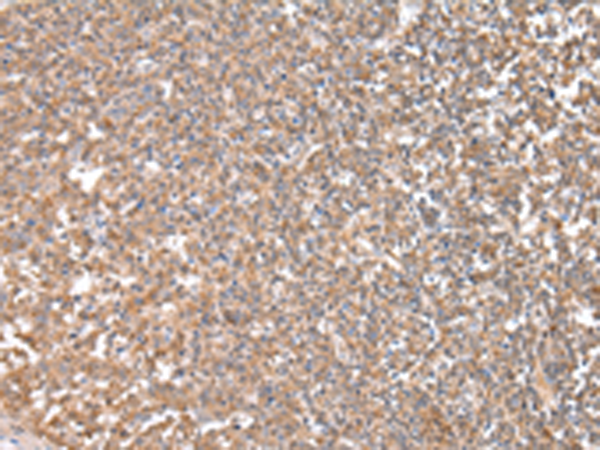

分类: 科研抗体货号: P12488别名: FB22; HM89; LAP3; LCR1; NPYR; WHIM; CD184; LAP-3; LESTR; NPY3R; NPYRL; WHIMS; HSY3RR; NPYY3R; D2S201E应用: IHC反应种属: Human, Mouse, Rat